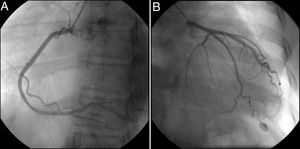

A 34-year-old female with no cardiovascular history presented chest pain within two hours of a 38-week-gestation cesarean delivery. She was hemodynamically stable. Serum troponin I (2529.6 ng/l, cutoff 15.6 ng/l) and brain natriuretic peptide (508 pg/ml, cutoff 100 pg/ml) were elevated. Her electrocardiogram showed normal sinus rhythm (heart rate 50 bpm) without ischemic changes. Transthoracic echocardiography (TTE) revealed increased left ventricular (LV) dimensions, left ventricular ejection fraction (LVEF) 47%, global longitudinal strain (GLS) -19% with marked basal impairment, moderate central mitral regurgitation (MR) with apical displacement of the leaflet coaptation point, and normal right ventricular dimensions and function (Figure 1A, Table 1 and Video 1). Invasive coronary angiography revealed no lesions (Figure 2), while myocarditis was precluded by the absence of infection and pericardial effusion and normal serum C-reactive protein levels.